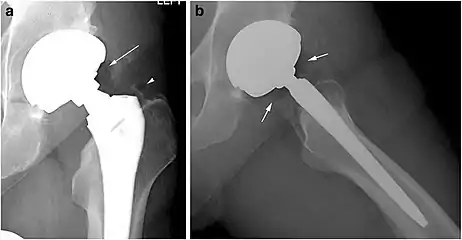

Other thoracic